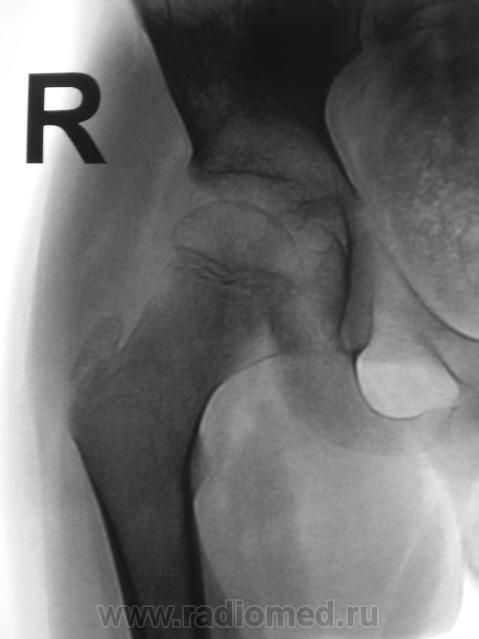

Пациент направлен на конрольное рентгенологическое исследование средней трети бедренной кости с целью оценки консолидации. Ранее - первичный снимок пациент был направлен на рентгенографию средней трети бедра, что и было сделано. Но, при производстве "контроля" рентгенолаборанты захватили тазобедренный сустав в прямой проекции, и возникли неясные сомнения по поводу головки, да и вообще...

Какой-то «змей 2х-головый» и впадина не слава богу. Надо или детских рентгенологов ждать или вторую проекцию делать.

Отлично все срослось. А что не нравится в головке? Остеопороз? Может быть после длительной иммобилизации.

Сама головка не нравится, особенно её нижне-медиальный отдел.

Согласна, что-то и меня в глазах головка бедра двоиться.

Пожалейте ребенка, не надо томографировать. Все укладывается в норму. Просто головка еще маленькая, а медиально - это шеечная шпора. Уж если не верите, снимите оба сустава одновременно.

Вероятно остеопороз головки от функционального щажения, разрушений не видно, капсула (мягкие ткани) параартикулярно - в норме...

А в нижней половине вертлужной впадины всё ОК?

Согласен с теми коллегами которым, в нижнем квадранте вертлужной впадины видится фрагмент головки бедренной кости.В принципе тоже против "линейки", но "змея " добить надо.Почему бы не выполнить ультрасонографию сустава?

Интересная дискуссия. Жаль с опозданием увидел (однако же, много времени уходит, пока всё на сайте просмотришь). На мой взгляд, патологии головки нет, без фрагментации, проекционно пересекается с тенью обызвествляемого Y-хряща. Под головкой медиально, несомненно, есть остеопороз, придающий нечеткость картине. Впрочем, регионарный остеопороз имеет место вследствие закономерной атрофии после иммобилизации. Сюда же наслаивается субстрат т.н. фигуры серпа, еще не оформленный. Впадина нормальная. Кость срослась - замечательно, всем бы такие результаты. Реабилитация обязательна.